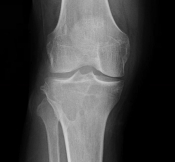

What’s the Diagnosis? Gepost op 19 april 201819 april 2018 door netwerkvsseh What’s the Diagnosis? @emdaily.cooperhealth.org Dit delen: Delen op X (Opent in een nieuw venster) X Share op Facebook (Opent in een nieuw venster) Facebook Delen op LinkedIn (Opent in een nieuw venster) LinkedIn E-mail een link naar een vriend (Opent in een nieuw venster) E-mail Afdrukken (Opent in een nieuw venster) Print Vind-ik-leuk Aan het laden... Gerelateerd